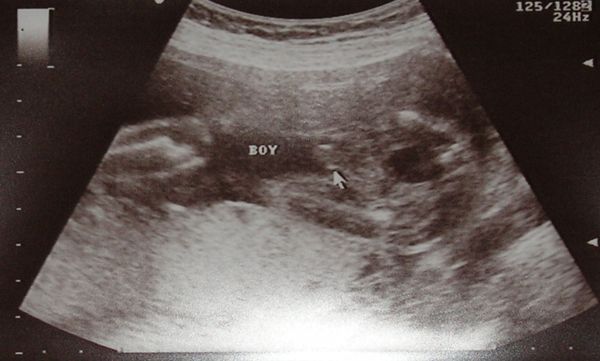

Első Milos Zétény (boy=fiú :wink: )

A második képen fent a keze látható Zetinek (Edus Milosnak, Zsiga Májlónak, Zsombi meg csak egyszerűen hööö-nek hívja), és fogja a buksiját. Gondolkodik, tehát van.